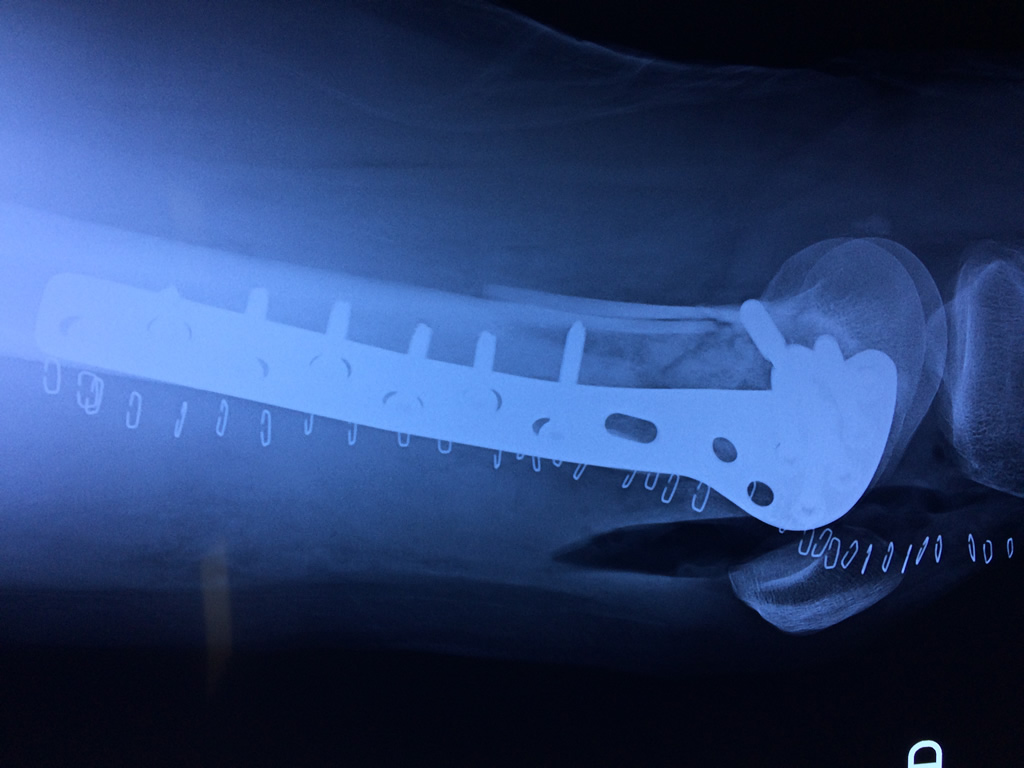

Cirugía de Cadera

El fémur es el hueso del muslo, el segundo segmento del miembro inferior. Es el hueso más largo, fuerte y voluminoso del cuerpo humano.